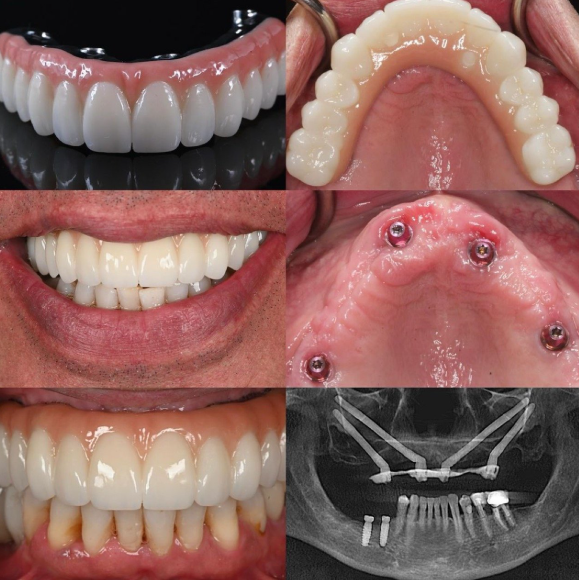

Em 2026, os implantes dentários de zircônia surgiram como uma opção totalmente cerâmica revolucionária para as zonas anteriores maxilar e mandibular, onde a estética, a harmonia dos tecidos moles e a previsibilidade a longo prazo são fundamentais. Ao contrário do titânio tradicional, a cor branca semelhante a um dente da zircônia elimina o sombreamento cinza através de biotipos gengivais finos, proporcionando pontuações estéticas superiores em rosa e branco, mantendo alta biocompatibilidade e baixa adesão bacteriana. Dados recentes de longo prazo confirmam taxas de sobrevivência que rivalizam com o titânio em casos cuidadosamente selecionados, com restaurações monolíticas de zircônia simplificando os fluxos de trabalho e reduzindo complicações. Este guia baseado em evidências sintetiza estudos clínicos de 2025 a 2026 para delinear avanços, seleção de casos e protocolos para resultados ideais na zona estética.

Os implantes de zircônia – principalmente policristalino de zircônia tetragonal estabilizada com ítria (Y-TZP) de uma ou duas peças – oferecem soluções sem metal que atendem às demandas dos pacientes por restaurações de aparência natural. Os avanços na modificação de superfícies (superfícies ZLA jateadas e gravadas com ácido) e nos projetos monolíticos CAD/CAM estreitaram a lacuna histórica na osseointegração e no desempenho mecânico, tornando-os ideais para pacientes com linhas de sorriso elevadas, biótipos finos e aqueles com sensibilidades metálicas.

Os implantes modernos de zircônia apresentam superfícies microrrugas otimizadas que promovem osseointegração comparável ao titânio em estudos de curto e médio prazo. A resistência à flexão excede 900 MPa, enquanto a tonalidade branca garante excelente transmissão de luz e fluorescência combinando com o esmalte natural da dentina. Coroas ou pilares monolíticos de zircônia eliminam os riscos de lascamento da faceta, com formulações de alta translucidez que agora rivalizam com o dissilicato de lítio na estética anterior.

A análise de subgrupo confirma que a zircônia se destaca na estética anterior: pontuações PES mais altas e visibilidade zero do metal, mesmo com recessão menor. Embora alguns estudos observem uma sobrevida global ligeiramente inferior à do titânio em cenários de alta carga, a seleção rigorosa dos casos e os protocolos de colocação tardia produzem resultados comparáveis ao titânio na zona estética.

As complicações permanecem baixas: nenhuma fratura de implante em múltiplas séries de longo prazo, problemas mecânicos raros com designs monolíticos e resultados favoráveis relatados pelos pacientes (estética VAS 8.6+).

Restauração : Coroas monolíticas de zircônia de alta translucidez – aparafusadas para facilitar a recuperação ou cimentadas em bases de zircônia/titânio. Protocolos adesivos (primers MDP) garantem a retenção. O ajuste oclusal via análise digital evita sobrecarga.

Esses protocolos, combinados com os refinamentos do material 2026, proporcionam uma sobrevida superior a 95% em aplicações anteriores quando as indicações são compatíveis.

Os implantes de zircônia na zona estética representam uma mudança de paradigma em 2026 em direção à implantologia totalmente cerâmica e centrada no paciente. Com taxas de sobrevivência em 10 anos de até 97,7%, níveis ósseos estáveis, estética superior e alta satisfação do paciente, eles oferecem soluções previsíveis e livres de metal onde a harmonia natural é mais importante. Ao alinhar as propriedades dos materiais com as demandas específicas de cada caso – biótipos finos, linhas de sorriso acentuadas e prioridades estéticas – os médicos alcançam resultados que rivalizam ou excedem as opções tradicionais, ao mesmo tempo que preparam práticas à prova de futuro.